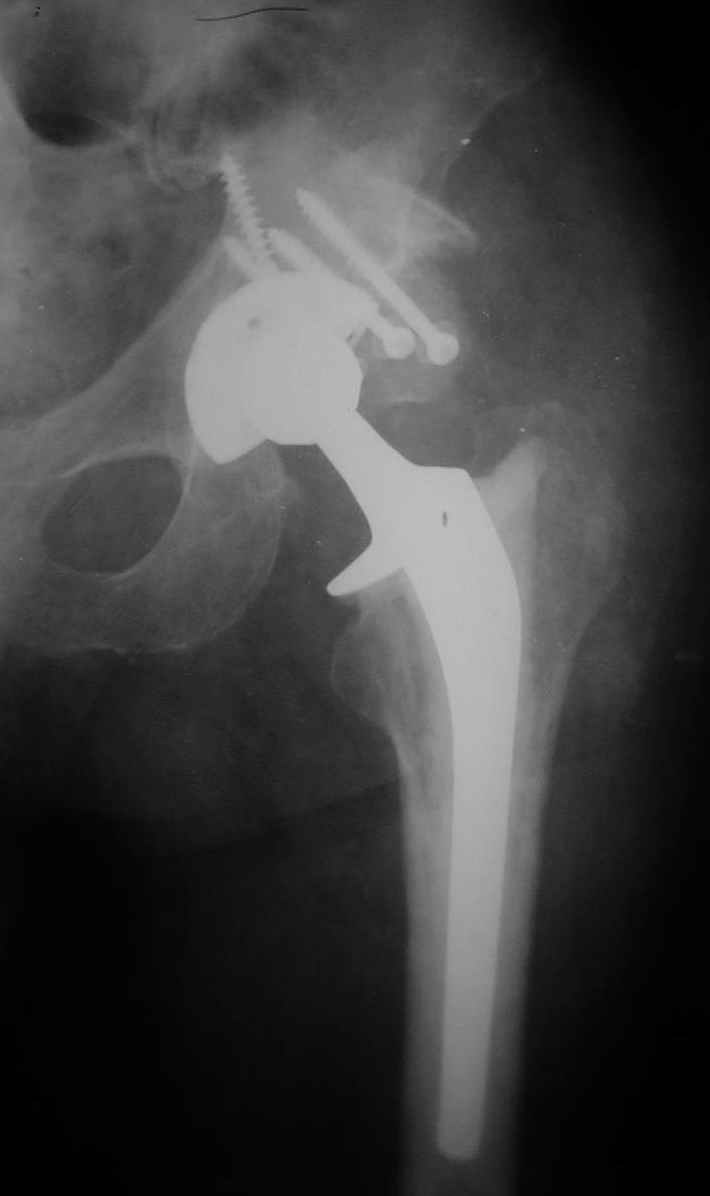

В институте совместно с фирмой Зиммер достаточно регулярно (практически ежемесячно) проводятся 2-х недельные циклы по различным вопросам эндопротезирования. Если есть возможность и желание, мы готовы поделиться с Вами нашим опытом, тем более есть что показать и что обсудить - в настоящее время ежедневно выполняется от 6 до 10 эндопротезирований коленного и тазобедренного сустава. В качестве примеров хочу показать 2 наблюдения, через 1 год и 5 лет после операции

1 год